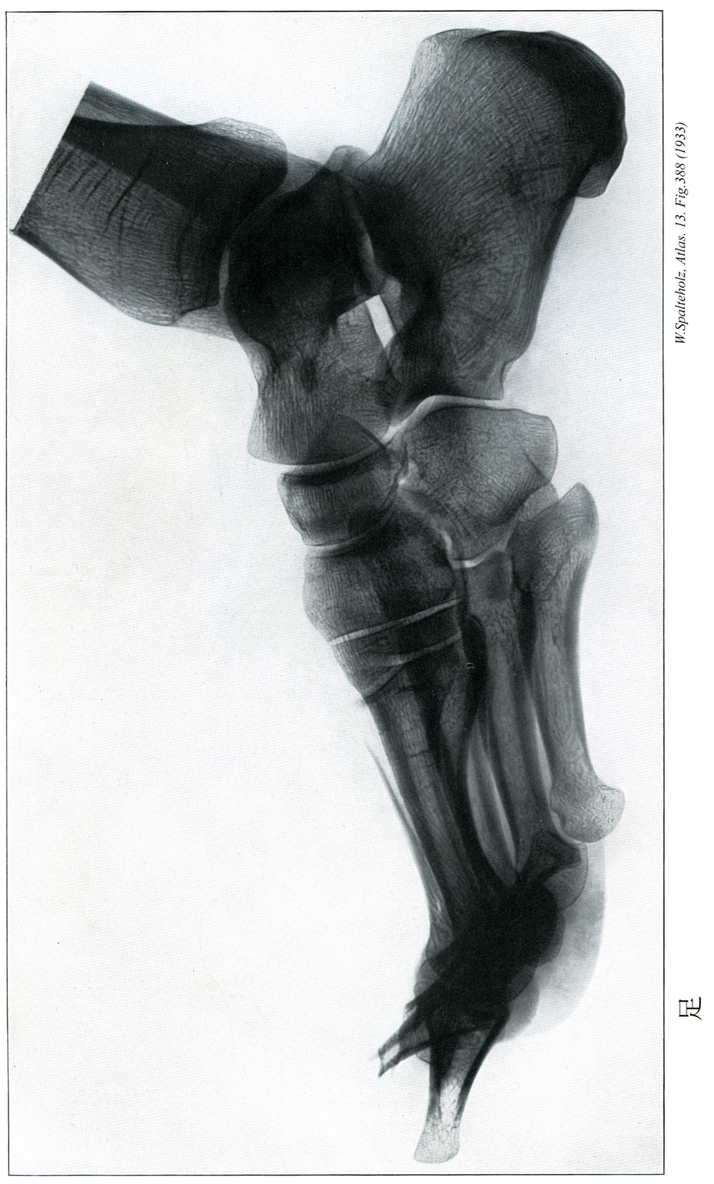

【Foot

足

Pes】

→(足根部、中足部および趾(足の指)にわけられる。足根部は足根骨(7個)、中足部は中足骨(5本)、趾は趾骨(14個)が基礎となっている。皮膚節において第四腰神経、第五腰神経、第一仙骨神経のレベル)